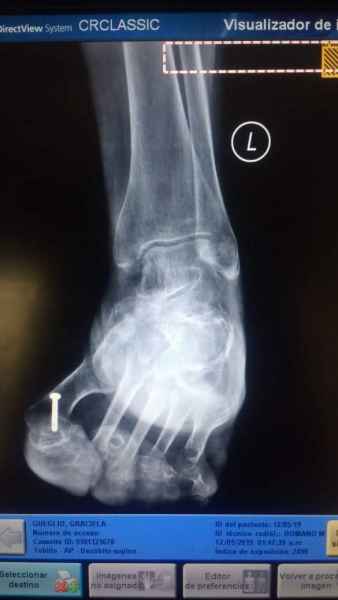

El pie es el órgano distintivo y característico de la especie humana, la única criatura que marcha erguida. El pie es una muy compleja estructura de arquitectura perfecta, adaptado a su función de apoyo, traslación, salto, con una riquísima sensibilidad que le permite detectar las más leves imperfecciones del suelo para estabilizar la marcha.

Tanto la estructura del pie como su funcionalismo que es la marcha, pueden ser asiento y manifestación respectivamente de alteraciones locales ó sistémicas, por lo que su cuidadoso examen resulta de extrema utilidad diagnóstica.

Dr. Juan Pablo Peralta, Ortepedia y Traumatología, Especialista en pies, Instituto Gamma